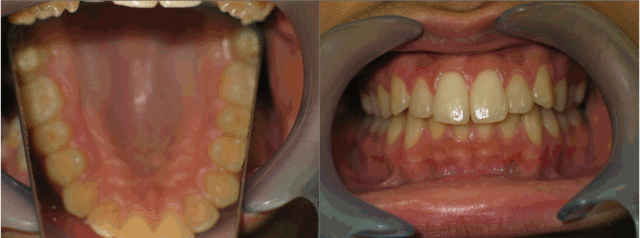

Photos intrabuccales.

03 palais blocic ambjby - Eugenol

04 coted coteg h0mpqk - Eugenol

Comme dsait catrose , il a une proalvélie de départ que tu as bien réduite, mais pas suffisamment. Je me ferai immoler par certains , d'autres peut etre prendront ma défense, mais sans extraction des 4 sup , je vois pas comment tu pouvais la réduire plus que tu as fait.

Les secteurs latéraux, c'est pour moi parfait.

Les rapports verticaux sont supers.

La vue frontale est esthétique.

Le futur au niveau récidives est peut etre un petit zizgag de l'arc incisif supérieur.

L'idéal serait le fil de contention le plus longtemps possible 13-23 et 33-43.